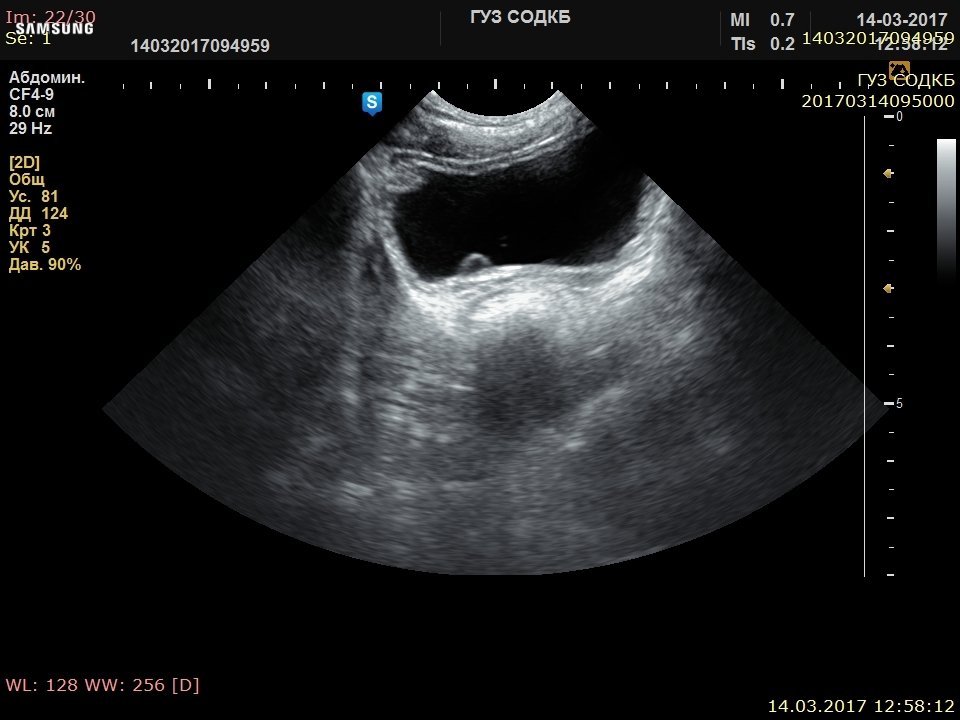

[RU] Ultrasound image №625: Gallbladder polyp in SDMR™ mode.

Echogramm was received by ultrasound scanner H60 (out of production).